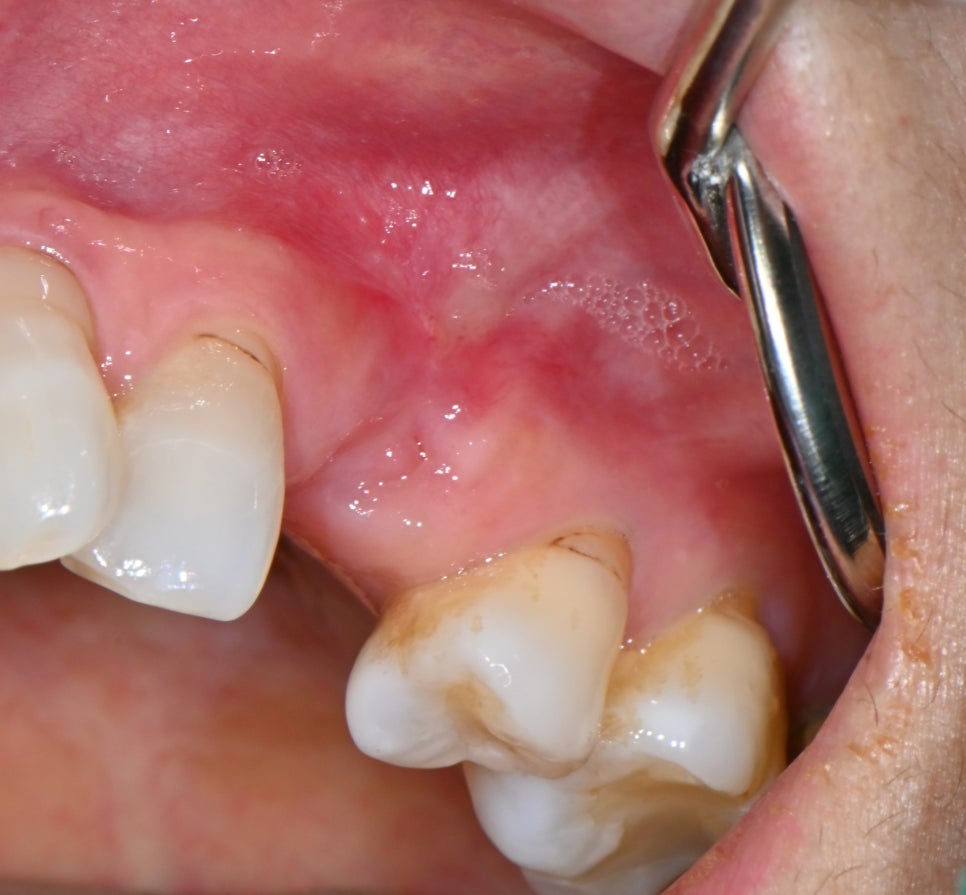

📸 Initial consultation photo

The patient developed inflammation after extraction at another dental clinic,

and was in a state where the gums were swollen and pus was repeatedly forming.

Initial front-view photo of the osteomyelitis patient

This photo was taken in more detail. When examined visually, there was a mass of pus inside the gum,

and the diagnosis was osteomyelitis.

In other words, the inflammation was not just on the surface; it had spread into the bone.

Initial oral photo of the osteomyelitis patient